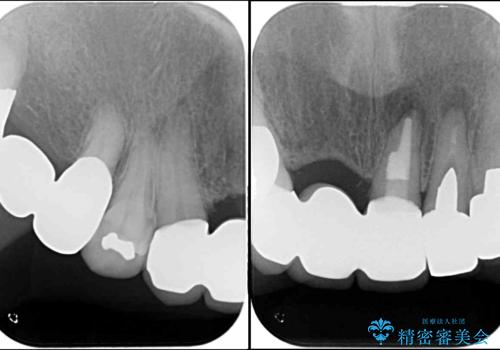

神経の抜かれている土台の歯は根管治療を行った上で、オールセラミックブリッジにより補綴することとしました。

仮歯に置き換えた時点で見た目が大きく改善され、人目を気にすることがなくなりました。

オールセラミッククラウンは、仮歯以上に快適な舌触りや、本物の歯のような外観となり、患者様には大変満足していただけました。